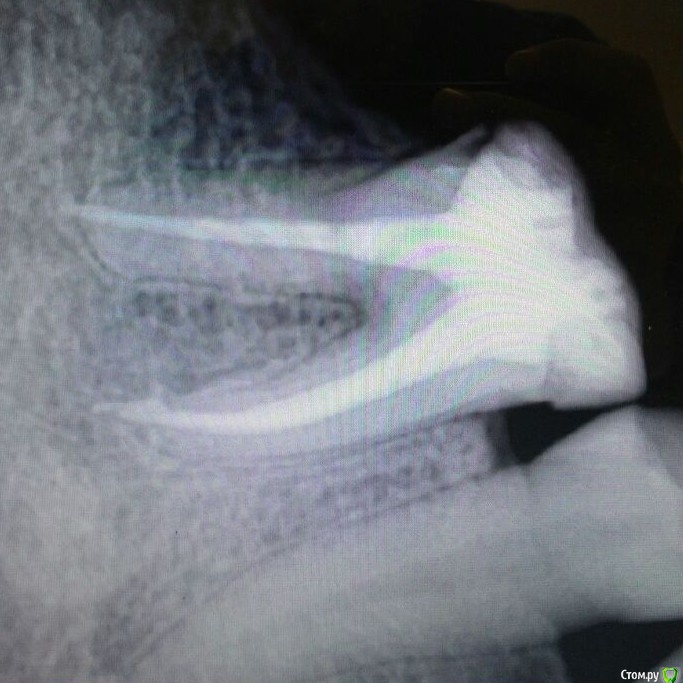

911 Опубликовано 13 мая, 2017 Поделиться Опубликовано 13 мая, 2017 Здравствуйте!Подскажите, возможно ли установить коронку на такой зуб? Он уже несколько раз леченный. Вот недавно куcок откололся. Откололась стеночка. Хирург эту стенку убрал. Что мне сейчас делать? Возможно ли этот зуб подготовить под протезирование? Или надо его полностью удалять?Заранее спасибо http://s019.radikal.ru/i619/1705/e0/822aa61d8240.jpg Ссылка на комментарий

red_butler Опубликовано 13 мая, 2017 Поделиться Опубликовано 13 мая, 2017 Если судить только по этому снимку, то зуб подлежит протезирование. Для однозначного ответа нужен очный осмотр. Ссылка на комментарий